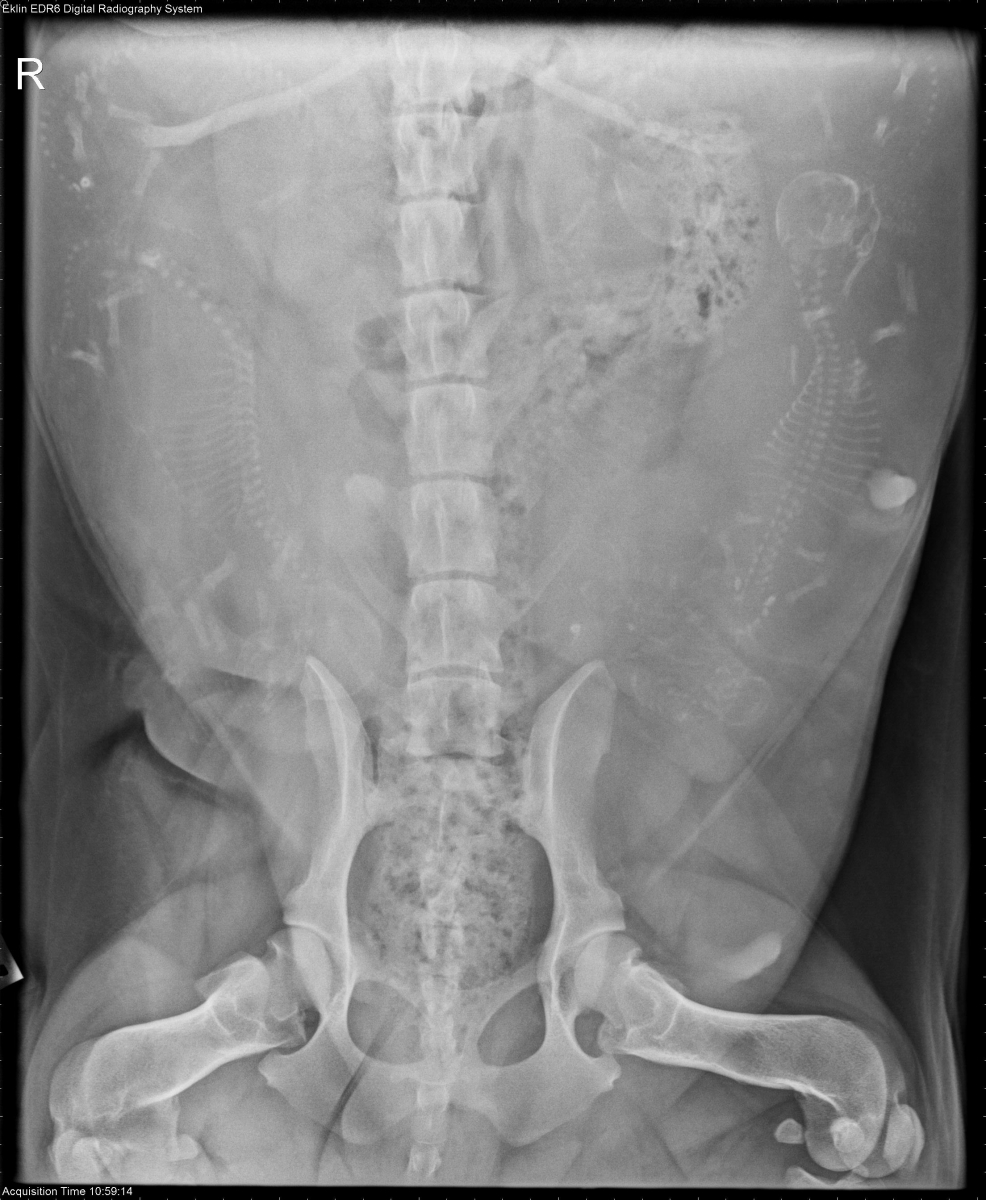

Today’s case is a 3 year old Bassett Hound, 55 days gestation, with a small amount of dark vulvar discharge. What is your assessment of the fetuses?

VD Abdomen

The abdomen is distended because of the gravid uterus. There are 5 well-mineralized feti consistent with the age of gestation. On the ventrodorsal projection, there is a small, collapsed, partially mineralized fetus just cranial to the left ilium. No gas is visualized in the uterus. The remainder of the abdominal organs appear normal.

At least one nonviable fetus, which likely died several weeks previously. There is no evidence of necrosis on the images.

An abdominal ultrasound was performed, and 3 nonviable and 5 viable fetuses were identified. There was no evidence of excessive fluid accumulation or gas in the uterus.